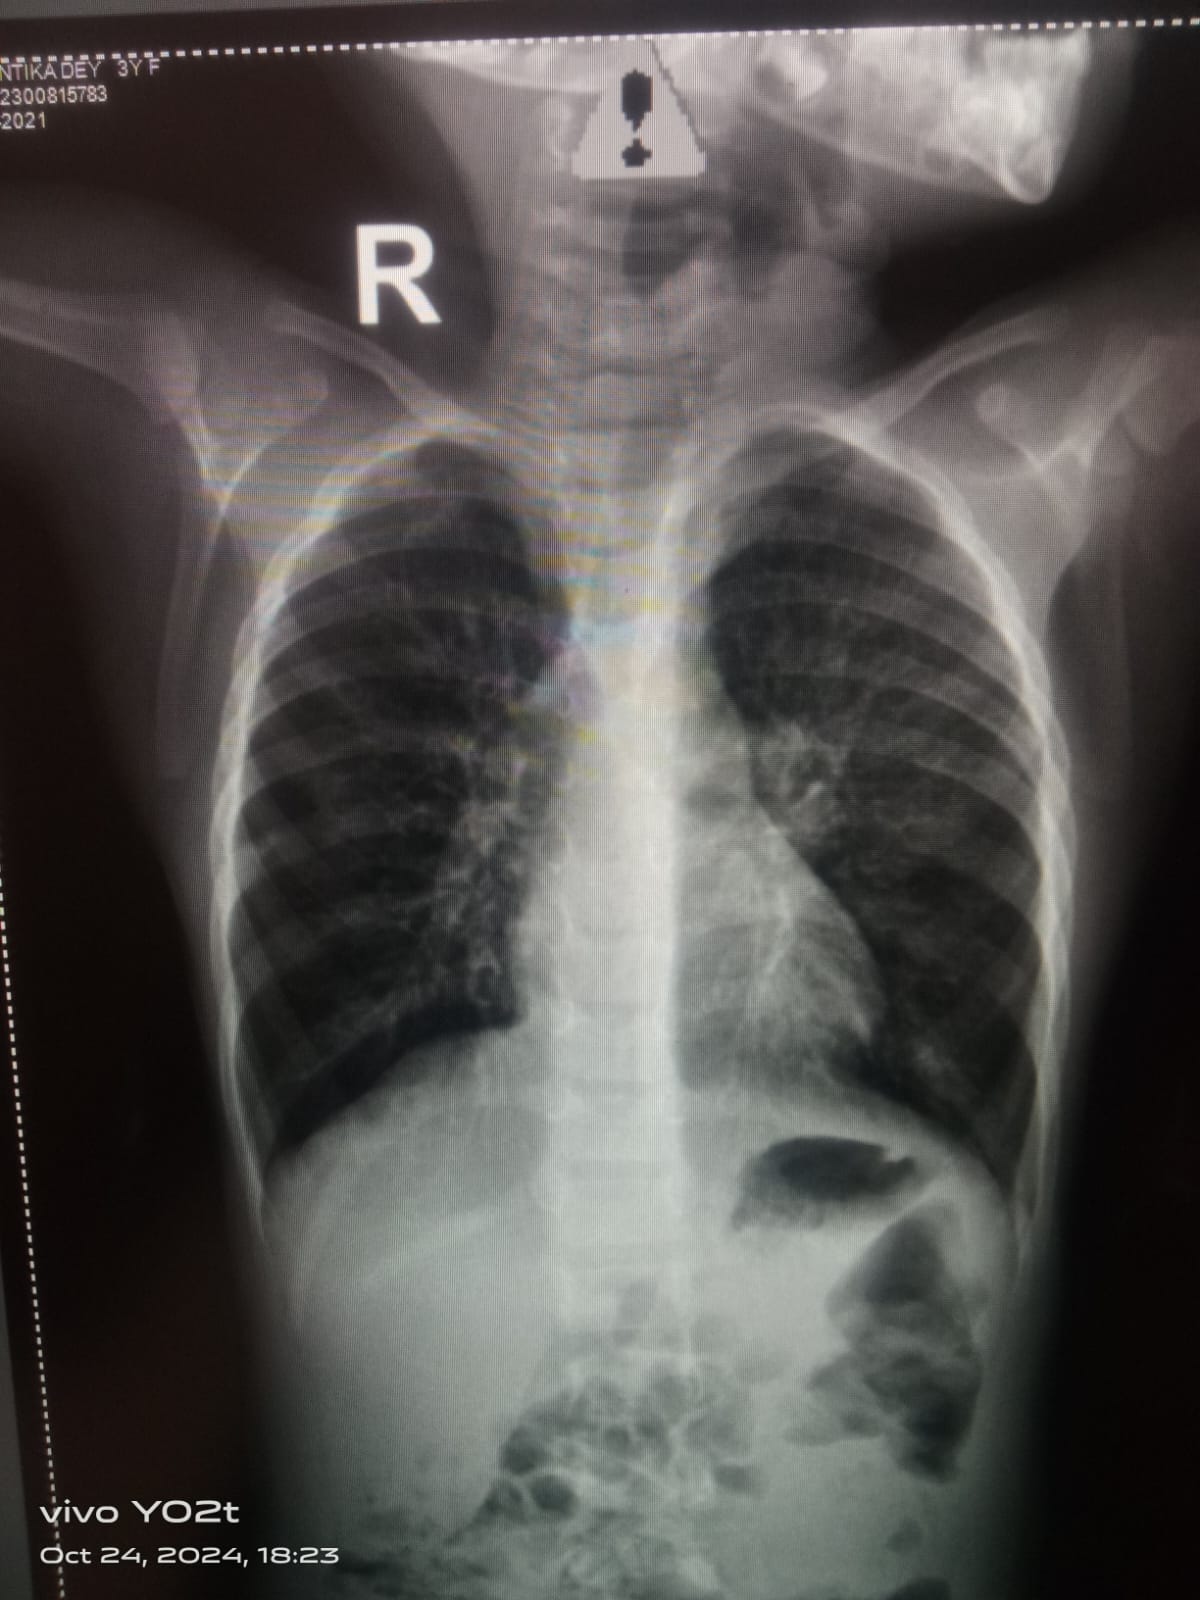

Current Case